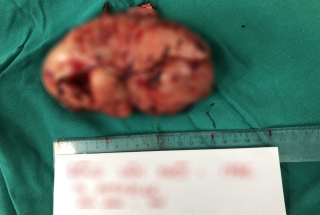

Các bác sĩ Bệnh viện Ung Bướu Hà Nội vừa phẫu thuật thành công cho một bệnh nhân mang khối u trong mạc chằng rộng kích thước “khổng lồ” với đường kính gần 30cm, nặng tới 6kg. Ca phẫu thuật diễn ra vô cùng căng thẳng do khối u ở vị trí phức tạp gây dính tạng và tăng sinh mạch máu khiến việc cầm máu gặp nhiều khó khăn.